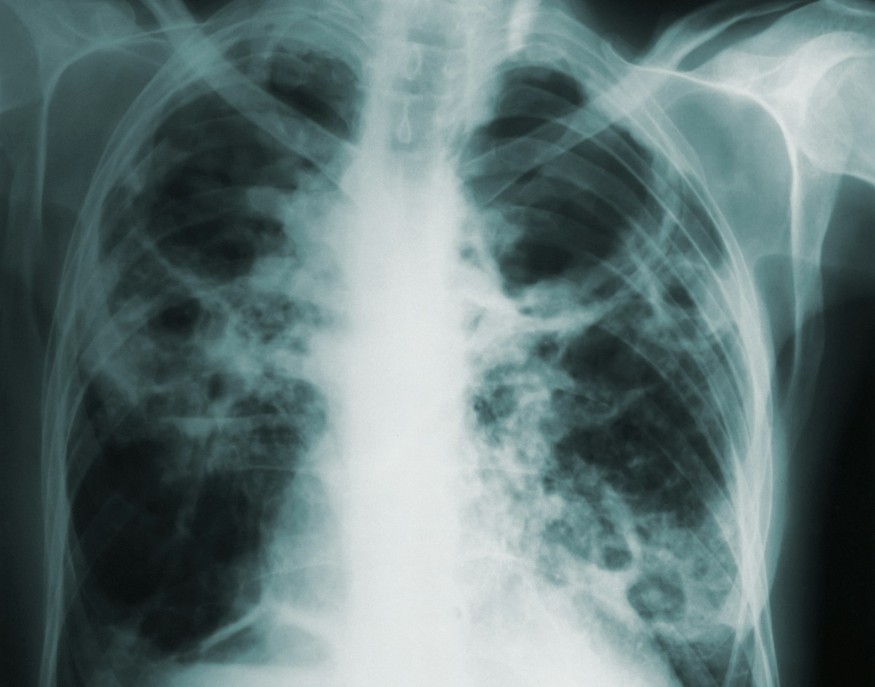

Public Health Wales has welcomed plans for a national lung screening programme, which will enable earlier diagnosis and treatment of cancers and ultimately save lives.

“Lung cancer is the leading cause of cancer death in Wales. Too often it is diagnosed late because it may not cause symptoms in its early stages. Screening gives us a chance to find it early, before symptoms appear.